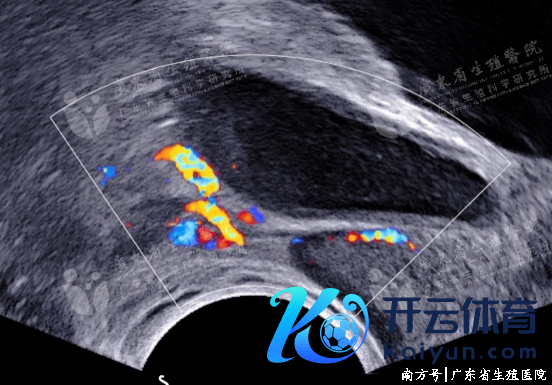

也称为继发性附睾梗阻,最常见的原因为附睾急、慢性炎症。附睾管或/和睾丸输出小管呈敷裕性、均匀性细网状彭胀。彭胀附睾管内可见眇小缺点状或黑点状强回声逐步流动。部分患者附睾管及睾丸输出小管呈管状彭胀,内可见密集高回声采集、逐步流动。

炎性附睾梗阻